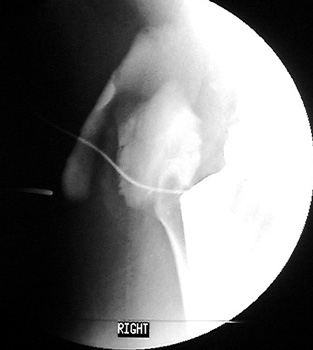

Aspiration of hip after removal of prosthesis. Needle placed

at femoral edge where fluid collects. Needle should not be placed in acetabular

area, which may not be fully intact, risking needle entry into pelvic cavity.